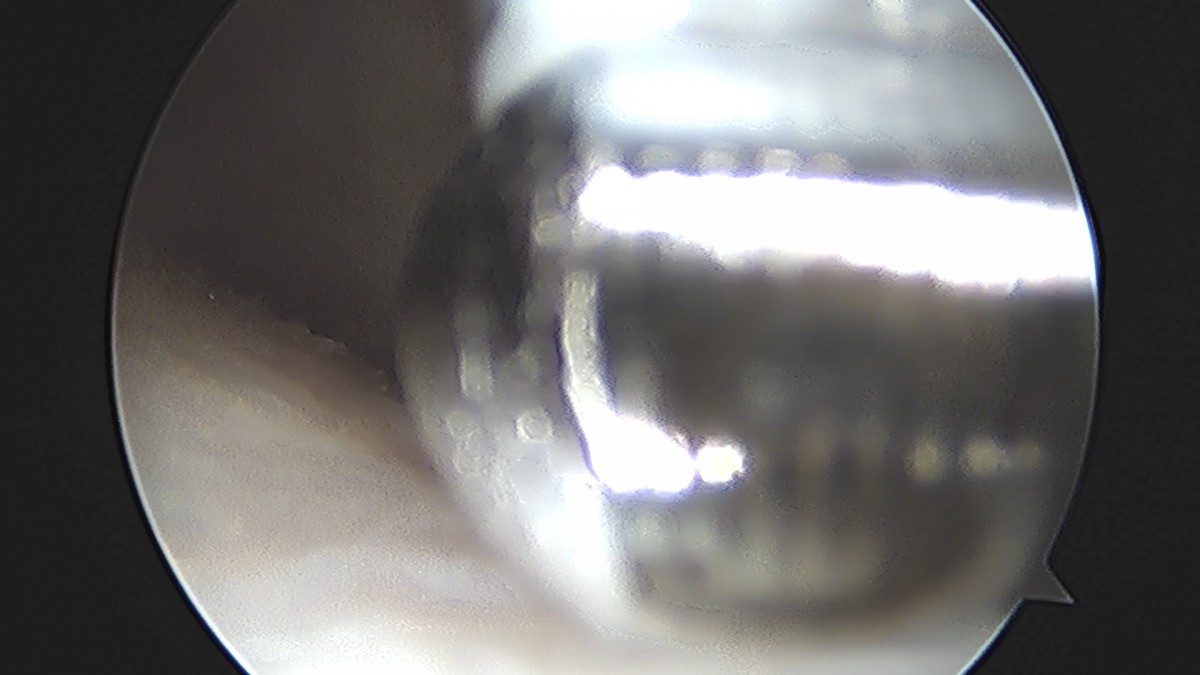

이재상원장님 무릎 반월상 연골판 절제술 이공O 환자

작성자 최고관리자 댓글 0건 조회 724회 작성일 25-09-16 15:43